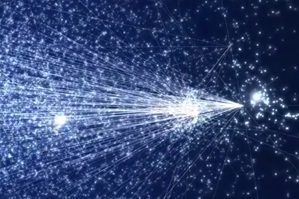

So the image on the left calls to my mind nebulae and distant galaxies…a sort of map of the universe, that infinitely large entity.

But in fact it’s a map of the microscopically small human cell. Doesn’t look a lot like the cell “maps” we’re used to though, does it? Instead of showing the location of the nucleus or the mitochondria, this map shows the genes that make up such bodies and the connections between them.

In a TEDmed talk earlier this year, physics professor Albert-László Barabási used this and other visualizations developed by research professor Mauro Martino to explain how the network of human genes is like the network of streets in Manhattan, and how mapping that network may eventually allow us to identify the clusters relevant to individual diseases the same way we can find a hub of art galleries or theaters in the Big Apple.